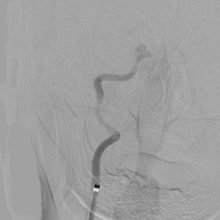

脳卒中担当医が常に診察することで、rt-PA 静注療法、脳血管内手術、脳神経外科手術の必要性を適切に判断し常に施行可能な体制を整えています。(写真は脳血管内治療の様子)

脳動脈瘤コイル塞栓術は、カテーテル(細いチューブ)を足の付け根の大腿動脈から挿入し、レントゲンで透視下にカテーテルを頚部の動脈まで誘導します。続いて、このカテーテル内にマイクロカテーテルと呼ばれる非常に細いチューブを通し、レントゲンで透視下に脳動脈瘤内まで誘導します。このマイクロカテーテルを通して塞栓物質(極めて細いプラチナ製コイル)を脳動脈瘤の中に詰め、脳動脈瘤内に血液が流れ込むのを遮断することで再破裂を予防します。

脳動脈瘤の中にコイルをつめて、血液が流れ込まないようにする

脳血管内治療とは、カテーテルと呼ばれる細い管を血管の中を通して病変まで誘導し、病変を治療する方法で、近年注目を集めています。脳血管内治療の特徴は何と言っても「切らずに治す」ことです。そのため基本的には局所麻酔で可能であり患者様の負担が非常に小さく、治療後の安静期間も少ないため入院期間も短くなります。 脳血管内治療は主にくも膜下出血や脳梗塞のような脳卒中の治療及びその予防に使われています。くも膜下出血の原因となる脳動脈瘤に対しては従来全身麻酔下での開頭手術で治療されていましたが、当院では患者様の状態や脳動脈瘤の位置、大きさ、形状によって、開頭手術と脳血管内治療のうち最適と思われる治療手段を選択して治療するようにしています。 また、脳梗塞に対しては、発症から4.5時間以内であればtPA静注療法と言う血栓を溶かす薬によって治療を行った上に、MRIにて脳の主幹動脈(内頚動脈や脳底動脈など太い動脈)の閉塞が見つかれば、脳血管内治療により速やかに血栓を取り除くことによって脳梗塞の悪化を止めるだけでなく、劇的な神経症状の改善を期待できるようになっています。